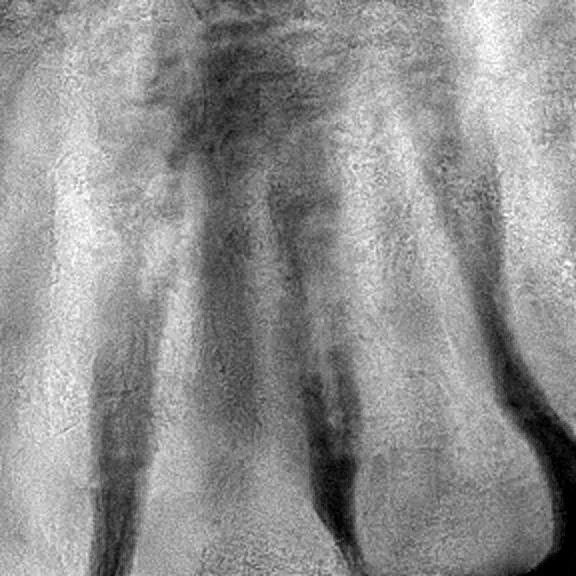

One of the most meaningful updates from this trip was seeing the success of a previously completed anterior root canal on Sandro, performed during a prior visit. His restoration is holding strong, the surrounding tissue is healthy, and his follow-up X-ray looked excellent—a beautiful reminder of the lasting impact of quality care.